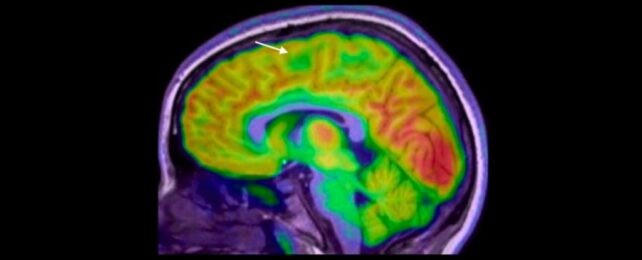

在儿童癫痫诊治中,一项澳大利亚研究展示了一个人工智能工具,能够检测极小、极易错过的脑部畸形,帮助患者更快获得可能改变命运的手术。 专家指出,癫痫的病因多样,但约有三成病例与脑部结构异常相关。这些异常往往在MRI上被漏看,尤其是最小的病灶,常隐藏在脑回褶皱的深处。

由墨尔本皇家儿童医院的 Emma Macdonald-Laurs 率队,研究人员让AI工具学习儿童脑部影像,以发现直径如蓝莓般大小甚至更小的病变。 她说:‘工具并不替代放射科医生或癫痫医生,而是像侦探一样,帮助我们更快拼凑线索,从而提供可能改变生活的手术。’

研究对象包括皮层发育不良和局灶性癫痫患者。结果显示,80%的孩子在研究中此前的MRI都显示为正常。 当研究人员将AI结合MRI与另一种成像技术 PET 时,诊断的成功率分别达到94%和91%(分组数据)。